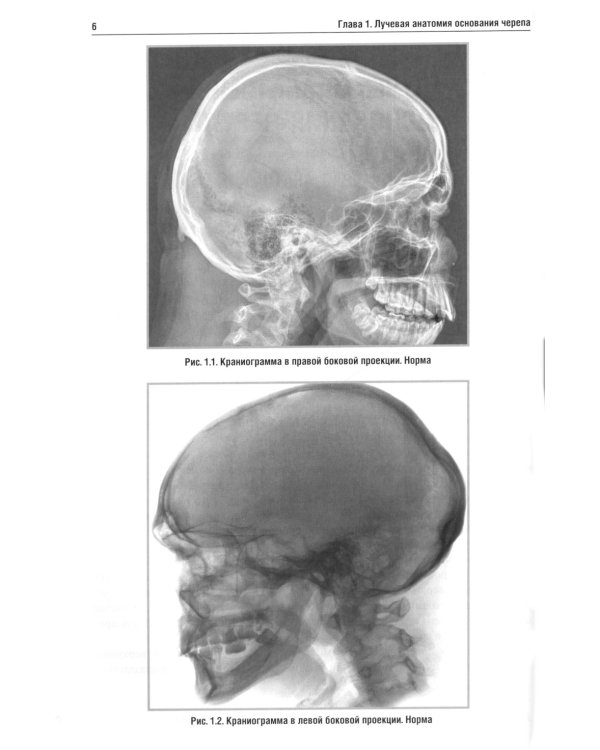

В учебном пособии изложена нормальная лучевая анатомия основания черепа по данным рентгенологического исследования, КТ и МРТ. Вторая и третья главы посвящены описанию лучевой семиотики наиболее часто встречающихся заболеваний основания черепа и мостомозжечкового угла, в которых представлены данные рентгенологического исследования, КТ и МРТ. Даются рекомендации по тактике лучевого исследования, приводится дифференциальная диагностика. Рассматриваются вопросы этиологии, патогенеза, морфологии и клинические проявления заболеваний. Для врачей, обучающихся по лучевой диагностике, нейрохирургии и неврологии. Пособие может быть рекомендовано для подготовки в системе последипломного профессионального образования.| Издательство | Элби |